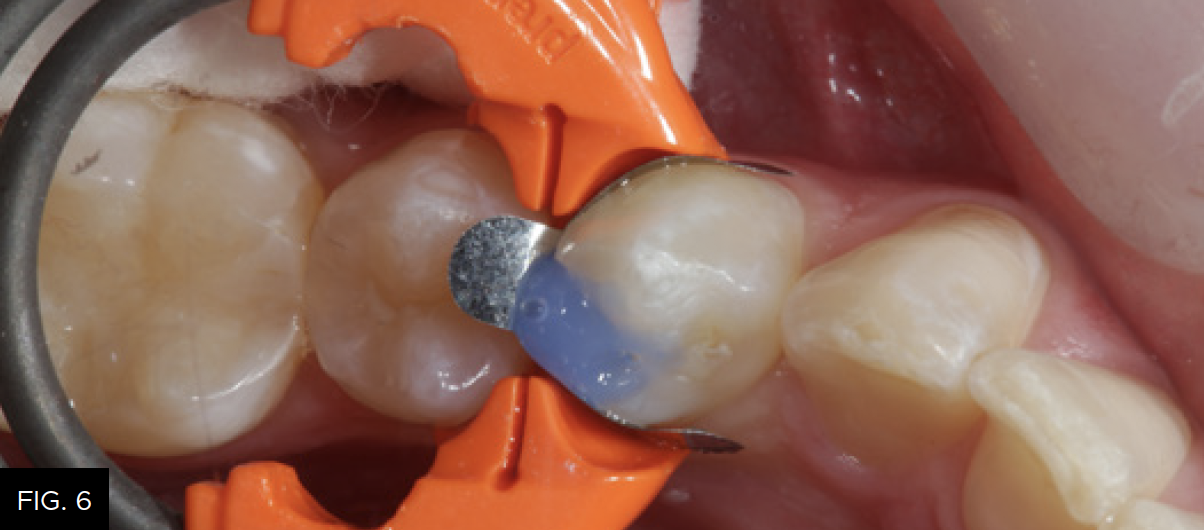

The sectional matrix (DualForce, Clinician’s Choice) is shown in place on tooth number 21 (34). Note the precise gingival seal due to the DualForce Active-Wedge and the accuracy of the adaptation of the matrix to the vertical walls of the preparation that will help eliminate flash and excess after composite placement.

A fifteen second total-etch protocol, 10 seconds on enamel margins and 5 seconds on dentin surfaces is performed using a 37% phosphoric etchant.

(FIG. 6)

Total-etch with 37% phosphoric acid (Max Etch, Clinician’s Choice) is performed for 15 seconds, then completely rinsed with water. Any excess remaining moisture is removed with the high-volume suction device (not the air syringe!) to avoid over desiccation and collapse of exposed collagen, which could lower the bond strength of the adhesive to the dentin.